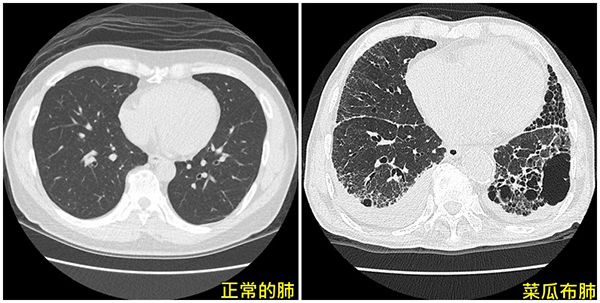

亞洲大學附屬醫院胸腔內科主治醫師郭家維表示,特發性肺纖維化是一種慢性、漸進性間質性肺炎,好發於50至70歲有吸菸史的男性,因患者肺部外觀和肺部電腦斷層影像如菜瓜布般呈現一絲絲的纖維,故又稱為「菜瓜布肺」,臨床症狀表現包括慢性咳嗽、漸進性活動性呼吸困難,且有些病患合併出現杵狀指(手指頭如鼓棒末端)。